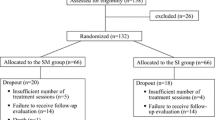

Eleven male Sprague Dawley rats (450–500 g; ~ 8.5–9 months old) were used for these studies. All experimental protocols were approved by the Institutional Animal Care and Use Committee of the University of Louisville.

Six rats underwent bilateral cryoinjuries to the belly of the mylohyoid muscles and were followed for 1 and 2 weeks post-injury to assess licking and swallowing function. Animals were initially anesthetized with isoflurane (2–3%) via inhalation and then transitioned to Ketamine (90 mg/kg) and Xylazine (9 mg/kg) with Atropine (0.05 mg/kg) via intraperitoneal (IP) injection. Buprenorphine 0.01–0.05 mg/kg was provided for analgesia for 3 days after injury. The mylohyoid muscle was surgically exposed via longitudinal incision and the anterior digastric muscle was bluntly dissected at the midline. The flat end of a cryoprobe (2 mm in diameter; Cry-AC-3 B-800, Brymill Cryogenic Systems; UK) was chilled by infusion of liquid nitrogen and applied to the surface of the exposed mylohyoid muscle for 30 s. The probe was then non-traumatically detached by allowing it to equilibrate to room temperature prior to removal to prevent further injury to the muscle. Following detachment, a second application in the contralateral muscle belly was applied for another 30 s. The incision was then sutured closed. Two weeks after injury, animals were euthanized with IP injection of urethane and transcardially perfused with PBS and 4% paraformaldehyde (PFA). Mylohyoid muscles were collected for histological analysis. For normal controls for histology, muscles were harvested from two uninjured rats.

Our study has several limitations. Our sample size was insufficient for detecting small/medium effects in EMG data. Although a depression in EMG amplitudes was observed across all the muscles tested, larger sample sizes are needed to study these differences. Sample size calculations were based on changes in the mylohyoid muscle. Similar studies in other animal models have indicated that three animals are sufficient at detecting differences with EMG using a within-subject design, which increases statistical power and reduces the sample size needed [62]. Furthermore, no sham-surgical control animals were included to determine if surgery itself impacted licking and swallowing function. The incision design (i.e., location at midline and short size) was chosen to limit the extent of skin injury, resulting in complete closer of the wound within 3–4 days post-surgery.